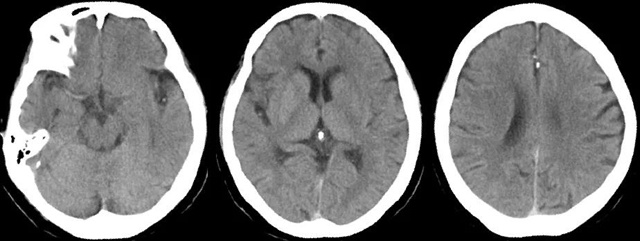

情况紧急,西南医科大学附属中医医院心脑病科副主任兼神经内科副主任刘天助博士接诊后,立即为刘婆婆开通了“脑卒中绿色通道”,紧急会诊,急诊进行头颅CT及术前造影。

结合基层医院CTP检查结果发现,刘婆婆后循环和左侧大脑半球灌注异常,梗死体积小于缺血区域1/3,基底动脉急性、左侧大脑中动脉M2段闭塞rtPA静脉溶栓未能开通,闭塞考虑为心源性栓塞可能。

经过一个小时紧张的手术,刘天助分别从婆婆基底动脉和大脑中动脉取出两块质硬血栓,刘婆婆的脑血管完全恢复了通畅。